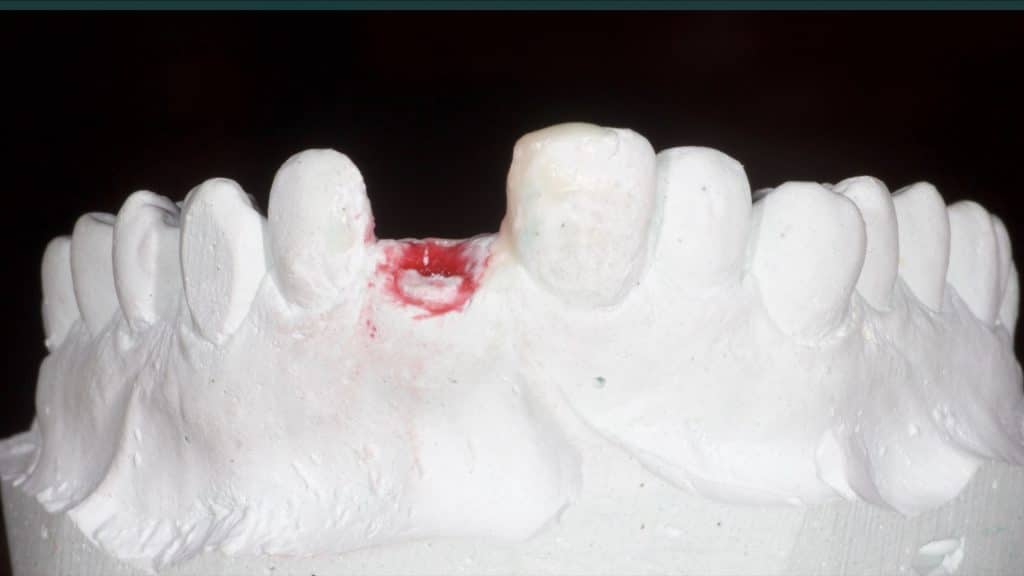

A 27-year female patient with dislodged Resin bonded FPD. She had that FPD for past few years, it had metal wings on palatal surfaces of UR1 and UL2 and a post like metal extension into the root canal of UL1. There was gingival abscess due to fractured root segment most probably due to extended metallic post like structure. Immediate implant placement (IIP) and Immediate restoration (IR) was planned for this patient.

Immediate post-op